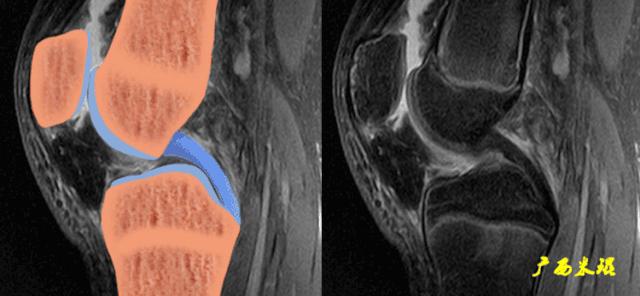

2、矢状面表现

矢状面PCL呈轻度迂曲的、凸面向后的弓形低信号影,边界清晰,粗细较一致,内部纹理清楚。股骨端信号常可局限性轻度增高,可能因此处韧带组织分散且滑膜较多、抑或是局部粘液变性或者魔角效应导致,不一定是损伤。

矢状面上弓形的PCL形成一个135°左右的夹角,PCL损伤后此角度一般都有改变。